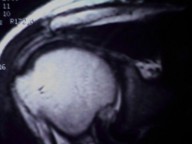

Axial MRI image to the left demonstrates two large vessels within the spinal canal, indicating a vascular malformation. Coronal MR image to the right shows curvature of the spine and dilated paravertebral vessels.